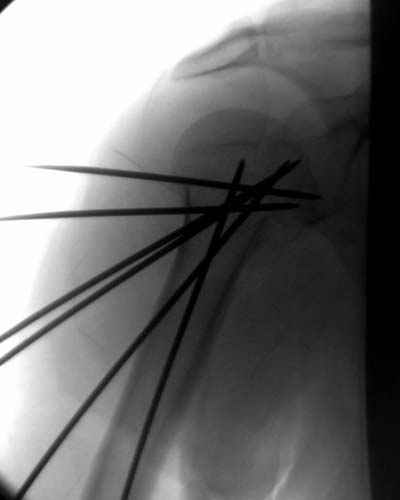

Здравствуй Женя. Во первых спицы, вводимые в головку плеча ретроградно, никогда не имели V-образную форму, если говорить о методике моей операции ЦИТО. Чтобы легче было запомнить Y-образную форму, вспомни крепление новогодних елочных шаров - очень демонстративно. Кроме того если ты внимательно посмотришь, то увидишь, что вся конструкция имеет некоторую кривизну по плокскости, величину, которой ты можешь задать сам. Сначала мы проводим проксимальный пучок, а в момент пересечения линии перелома мы

ротируем спицу таким образом, чтобы дистальный изгиб прямо противодействовал смещающим силам - поврот за ушко под контролем ЭОПа. Дистальный пучок стараемся провести так, чтобы его бранши расклинились и прошли по обе стороны предыдущего пучка, что создает дополнительное напряжение на

протяжении контакта. Для оценки правильности проведения спиц очень важно, чтобы ЭОП стоял строго перпендикулярно плоскости сустава, в противном случае - в рентгене есть эффект отбрасывания тени - прохождение косого луча дает удлиненное изображение спиыц и создается впечатление, что спица стоит уже в субхондральном слое. На первых операциях у нас было довольно частое несовпадение длины контрольной спицы и мы провизорно добавляли от 0,5 до 1,0 см уже на фиксирующем пучке. Входные отверстия лучше располагать по наружной и передней поверхности плеча на расстоянии не менее 2-х диаметров головки.

Такой выбор входных отверстий обусловлен прямой возможностью попадания в малый и большой бугорки за счет изгиба спиц по длине и отражения из от внутреннего кортикала проксимальнее точки введения. Поскольку анатомически бугорки не составляют артикулирующую поверхность, то некоторое выстояние спиц только усилит стабильность. Входное отверстие мы используем 6 мм в диаметре, для эффективного раскрытия петли-пружины. Спицы перед проведением

проверяем на достаточную эластичность и упругоустойчивость, мягкие спицы отбраковываем. В данном примере создалось впечатление, что одна бранша V-спицы скользнула по картикалу снаружи? Все это безболезненно можно переделать, расширив теже отверстия, изогнув спицы, повернув их в разные стороны и добавив еще пучки Y-ОБРАЗНЫХ, а не V-образных (эти пучки выталкивает, особенно если они прямые - пружина работает в обе стороны).

Сегодня взял больного повторно в операционную, не скажу, что повторная репозиция через неделю после первой попытки, была простая.

После удаления спиц попытался манипулировать отломками, но безуспешно, поэтому пришлось пользоваться периостальным элеватором, чтобы устранить смещение отломков и перепровести спицы. Проверил и перепроверил стабильность фиксации под ЭОПом, завтра Рг- будет готов, вот и поглядим....